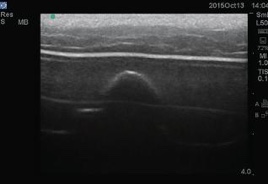

M193-2組織損傷超音波観察トレーニングファントム

褥瘡の生じやすい部位の皮膚・皮下組織の内部構造理解とエコー機器操作の基礎トレーニングに

短軸

長軸